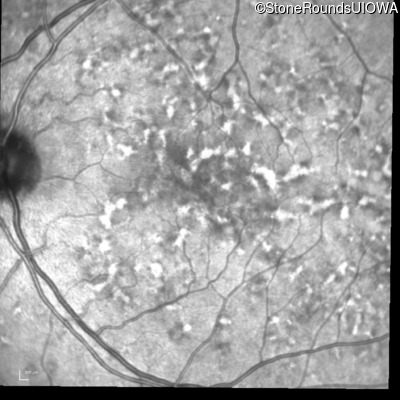

Blue Autofluorescence - Left - 20/32 sc

Exemplar